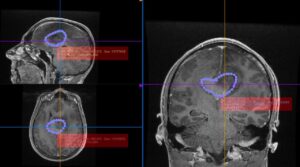

Salvamont România lansează un apel urgent la solidaritate pentru Geană Ștefan, salvamontist din Sinaia, în vârstă de 30 de ani, care trece prin cea mai grea misiune a vieții sale. După ani în care a salvat zeci de persoane de pe munte, Ștefan are acum nevoie de ajutorul comunității pentru a lupta cu o tumoră cerebrală agresivă.

Din cauza complexității cazului, intervenția chirurgicală nu poate fi realizată în sistemul medical de stat din România. Medicii au subliniat urgența situației: fără operație, șansele de supraviețuire sunt extrem de reduse. Singura soluție este o clinică privată specializată, însă costurile depășesc posibilitățile financiare ale tânărului salvator, fiind necesară o sumă de aproximativ 10.000 de euro.